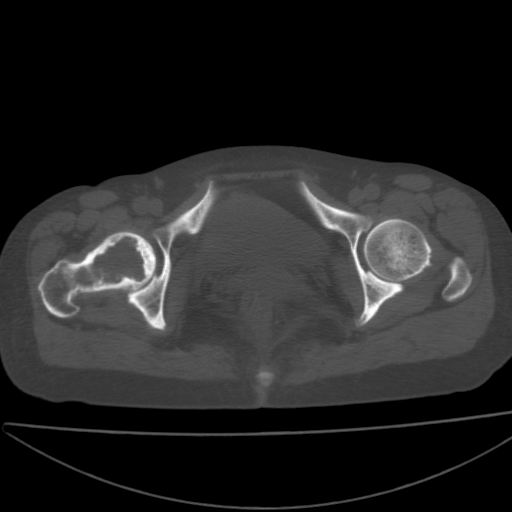

以下是引用xiaoniu在2008-9-6 8:22:00的发言:[br]右侧股骨颈囊性低密度,囊壁边缘硬化,中年妇女,首先考虑:骨囊肿。其次考虑动脉瘤样骨囊肿。[br][br][br][本贴已被 xiaoniu 于 2008-9-6 9:04:54 修改过]